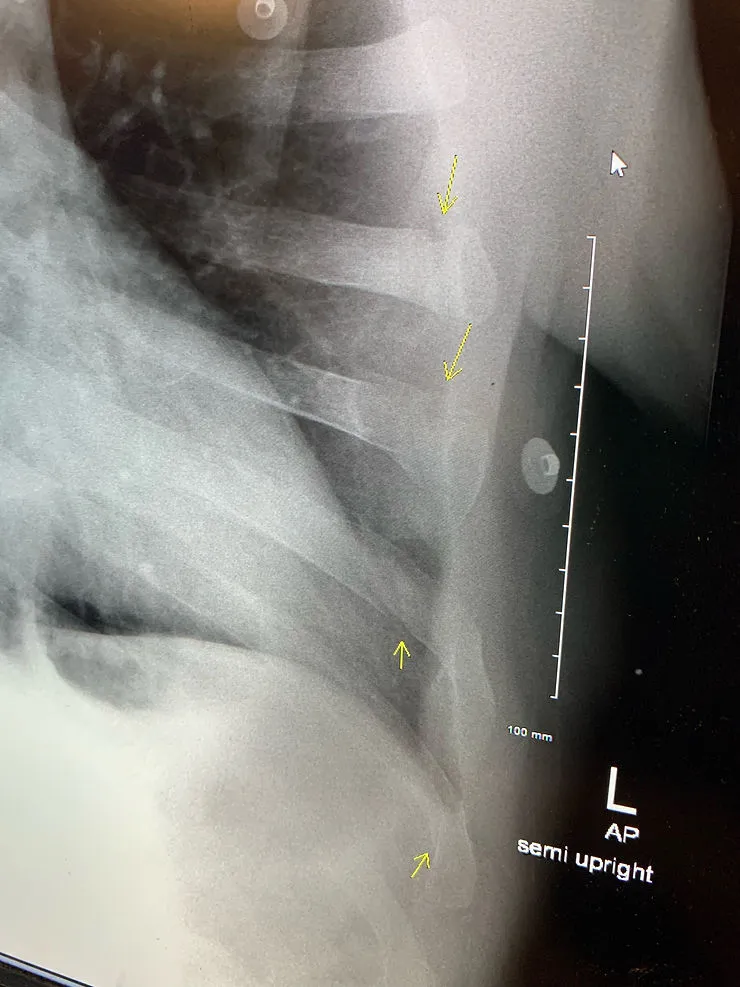

It was probably 30 minutes after all of that before I saw a doctor. She told us that the CAT scans of my head revealed no bleeding, and there were no breaks in my arms or legs. I had broken my 5th, 6th, 7th, and 8th ribs, but none of them were threatening organs. So while the pain was intense, even breathing hurt, there was no dramatic downside.

Turns out I had cracked by acetabulum socket. Yeah, me neither,. It’s right above the head of your femur bone where it connects to your hip,